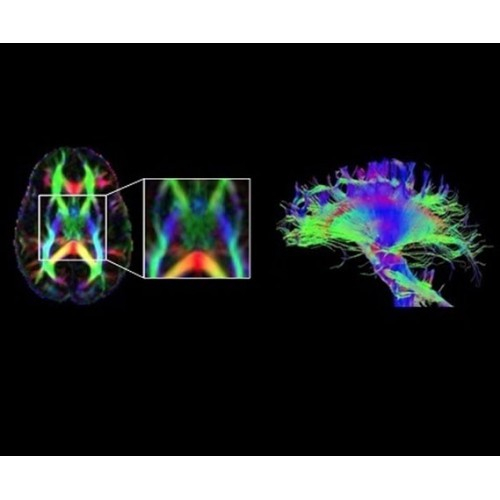

В систему SIGNA PET/MR встроены запатентованные детекторы кремниевого фотоумножителя (SiPM) и сверхчувствительные кристаллические сцинтилляторы на основе лютеция толщиной 25 мм. Благодаря этому обеспечивается исключительная чувствительность и возможность использования времяпролетной диагностики (TOF).

Кроме того, в результате использования технологии TOF и инновационной технологии реконструкции Q.Clear вы сможете добиться прекрасного соотношения сигнал/шум. А благодаря технологии нулевого времени эхо (ZTE) визуализировать костную структуру без ионизирующего излучения. Все эти разработки для улучшения качества сканирования и точности анализа помогут вам использовать весь потенциал ПЭТ/МРТ.

В системе SIGNA PET/MR есть все инструменты, необходимые для выявления маркеров разных заболеваний и для создания новых протоколов. ПЭТ/МРТ можно использовать совместно с мультиядерной спектроскопией в лаборатории in vivo для изучения быстрых биохимических процессов. Кроме того, PET ToolBox и набор инструментов Orchestra предоставляют персональный доступ к функциям реконструкции изображений для ПЭТ и МРТ, ускоряя и упрощая работу с необработанными данными.